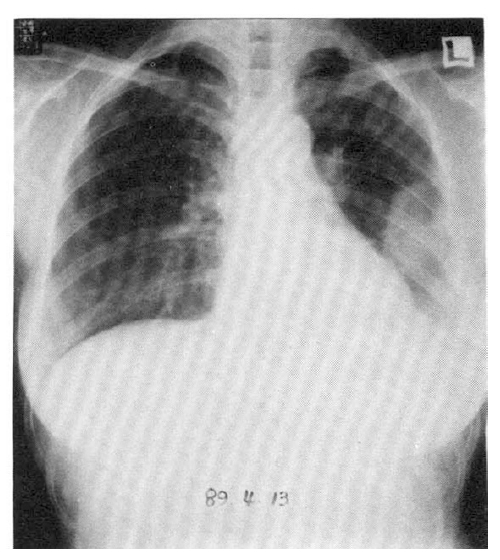

A chest X-ray revealed the shadow of a well-defined marginated mass in the left lung field (Fig. 1). A chest CT scan showed a mass lesion in the left anterolateral thorax broadly abutting the chest wall (Fig. 2). Gastrofiberscopic and colonofiberscopic examinations were normal. An abdominal ultrasonogram was normal. A bone scan was unremarkable. A percutaneous transthoracic biopsy was done. Histologically, the tumor tissue was composed of scattered osteoclastic-type multinucleated giant cells and large pleomorphic mononuclear cells (Fig. 3). The tumor cells showed positive immunostaining for vimentin. Stains for cytokeratin, epithelial membrane antigen were negative.

Fig. 3.

Microscopic section reveals solid tumor tissue composed of scattered osteoclastic-type multinucleated giant cells and large pleomorphic mononuclear cells. H&E Stain (×200)

MFH of the lung in histologic features similar to their soft tissue counterparts was classified according to the scheme proposed by Enzinger and Weisser16): storiform-pleomorphic, myxoid, inflammatory, giant cell ad angiomatoid. Our MFH of the lung showed scattered osteoclastic-type multinucleated giant cells and large pleomorphic mononuclear cells.